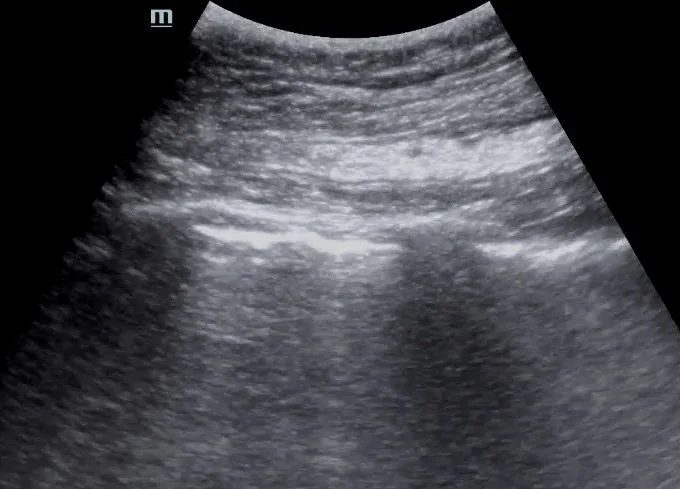

This post by Dr. Jordan DeAngelis reviews the use of point-of-care lung ultrasound to assess for pneumothorax, focusing on image acquisition, interpretation of lung sliding and the lung point, and practical tips to avoid common pitfalls.